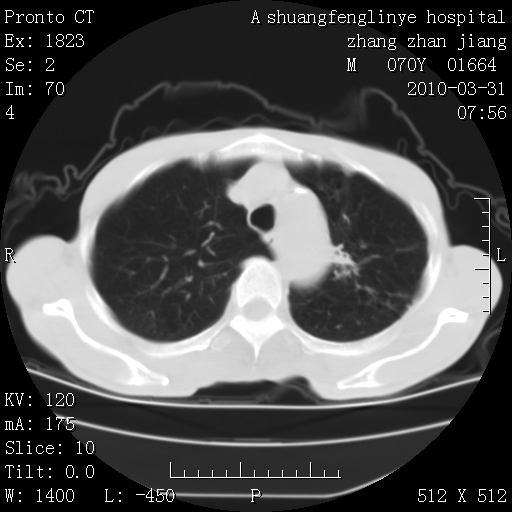

双上肺继发型tb并左上空洞形成,主动脉冠脉钙化。

1)两肺上叶继发性肺结核并左肺上叶空洞形成。2)冠状动脉及主动脉钙化。